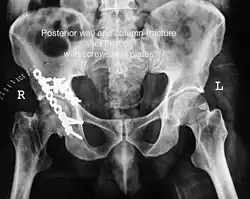

Posterior column and wall fracture as seen on 3D CT -

Posterior column and wall fixed using screws and plates